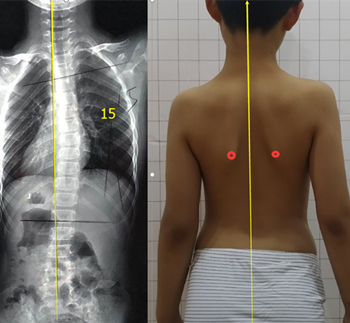

青少年脊柱側(cè)彎一旦被家長發(fā)現(xiàn),應(yīng)積極治療,阻止側(cè)彎進(jìn)一步加重。但也有一些孩子,在發(fā)現(xiàn)脊柱側(cè)彎后,由于醫(yī)生判斷失誤,家長不重視等等原因,沒有采取任何治療。發(fā)育期的孩子明顯增加較快,每個月基本增加1度。每年12度左右。

盡早展開學(xué)校脊柱側(cè)彎篩查,在30度以內(nèi)發(fā)現(xiàn),最后可以治療到低于20度。如果這樣,對孩子的影響幾乎可以忽略。